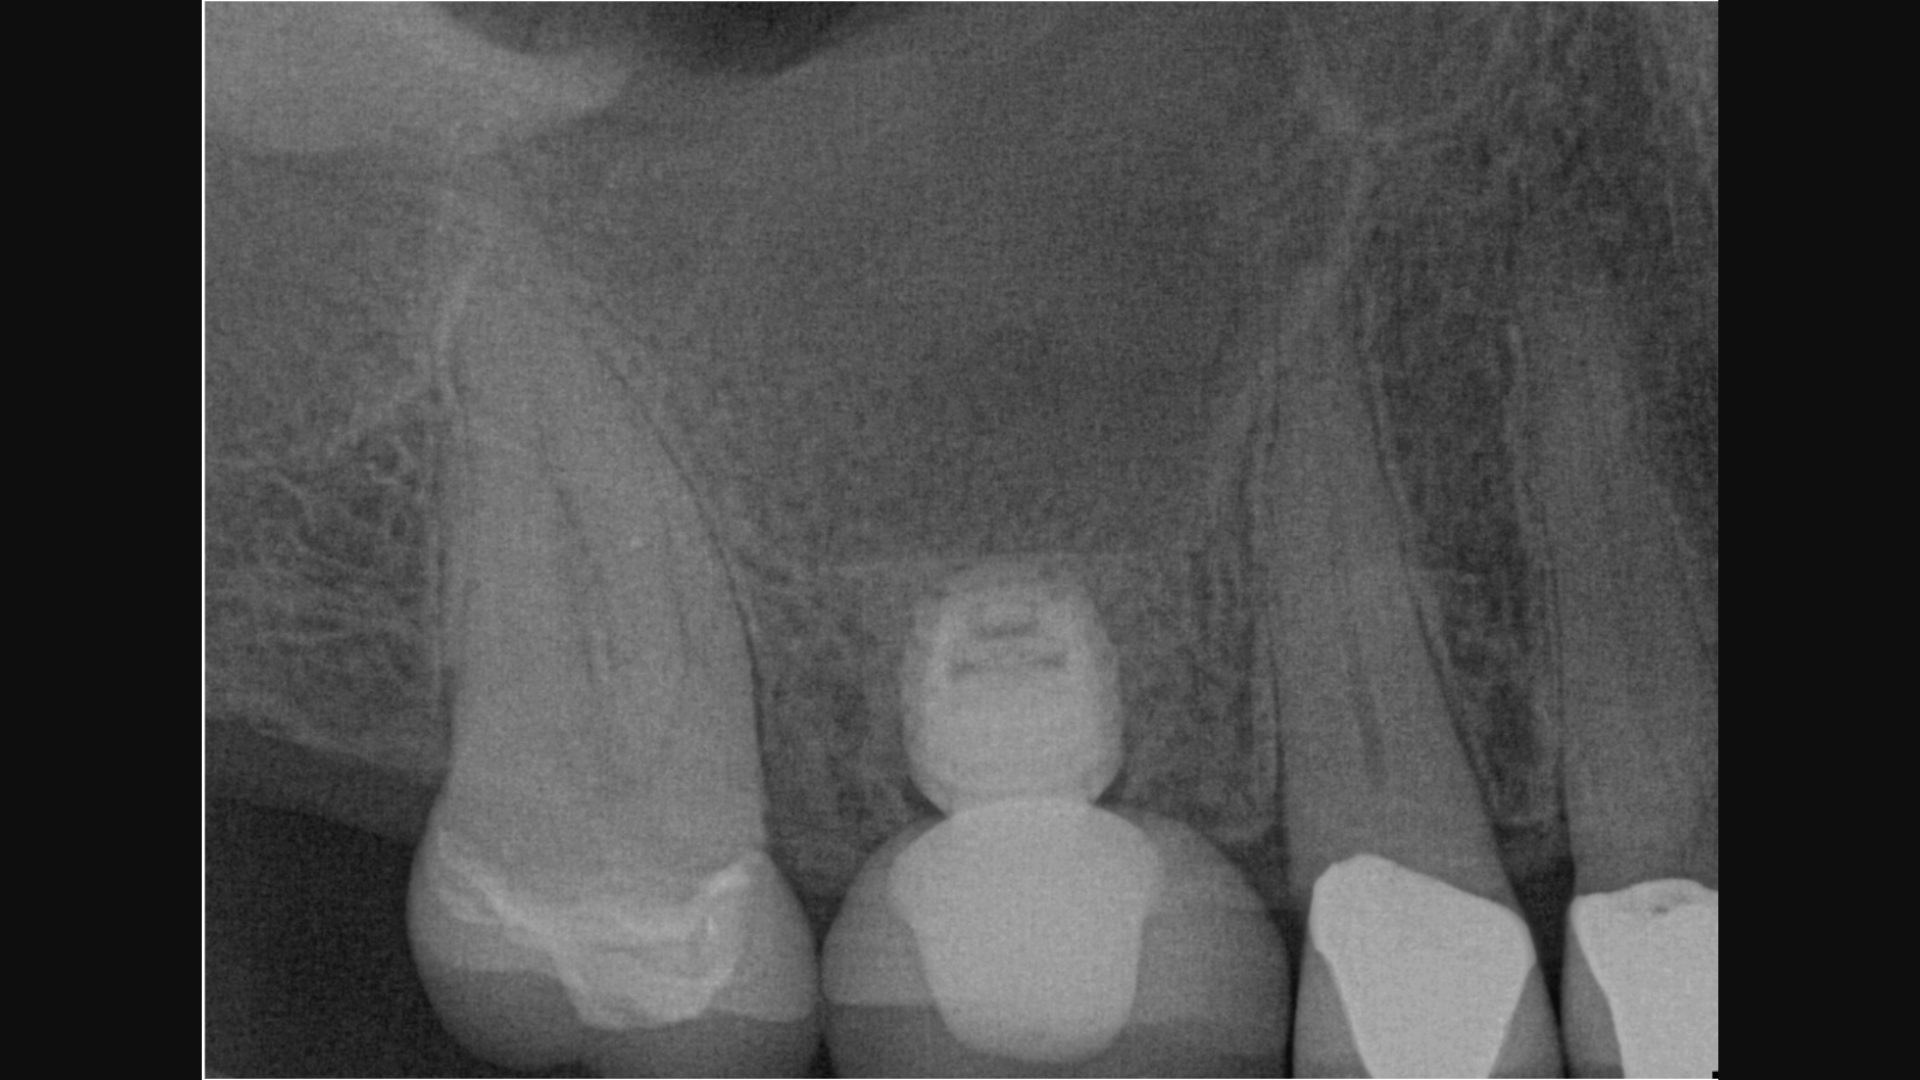

- How to diagnose the exact sinus lift method for each implant patient

- When a crestal sinus lift is indicated

- When a lateral window sinus lift is indicated

Because >50% of all upper molar implants need some sort of sinus lift.

- Gain clarity on sinus anatomy and what to look for when considering sinus lifts

- Fill out a measurements table to focus on the right data for diagnosis